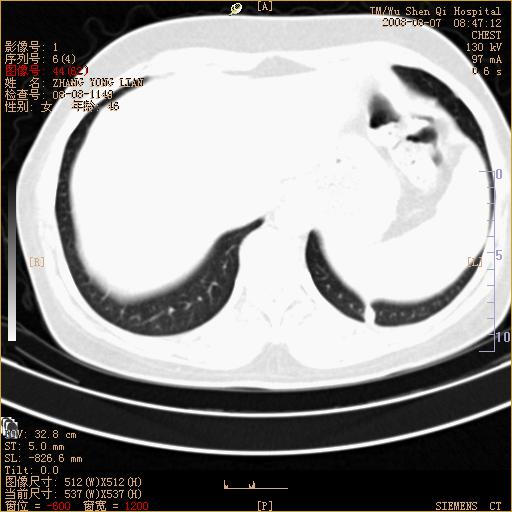

标题: CT15050:女,46岁,咳嗽胸痛一月余 [打印本页]

标题: CT15050:女,46岁,咳嗽胸痛一月余

纵隔窗没发全,左下肺近胸膜处结节。有长毛刺,纵隔淋巴结增大,不排除恶性病变。

考虑左肺下叶后基底段周围型肺癌伴纵隔淋巴结转移可能性大。

左下肺ca并纵隔及左肺门区淋巴结转移。

1)考虑左肺下叶后基底段周围型肺癌伴纵隔淋巴结转移。2)脾内低密度灶,性质待定;不排除转移瘤可能。